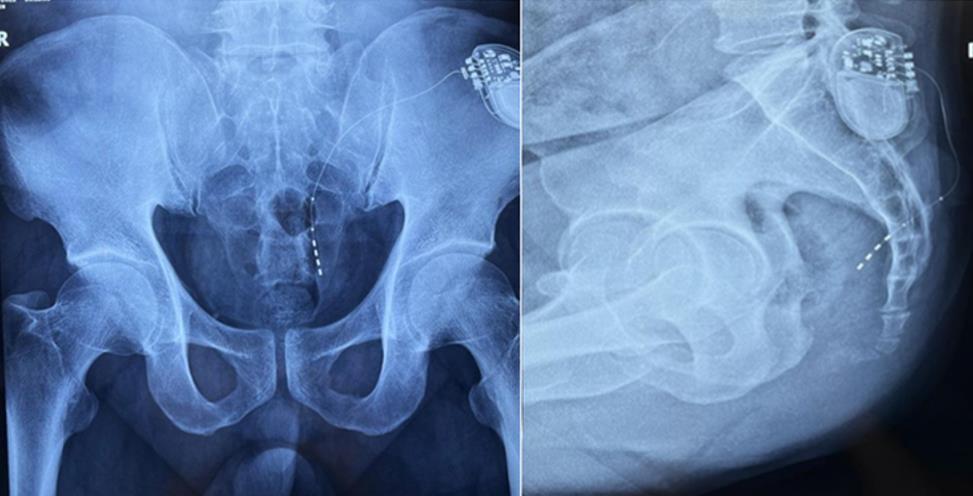

該患者兩年前被診斷患有膀胱過度活動癥(OAB),出現(xiàn)嚴(yán)重尿頻、尿急、尿細(xì)線等癥狀,醫(yī)生為其做了骶神經(jīng)調(diào)控手術(shù)。近期,患者癥狀又開始加重,生活質(zhì)量受到影響,為減輕癥狀,改善生活,患者前往南醫(yī)大二附院就診。衛(wèi)中慶主任及其團隊在查看患者病情后,決定重新調(diào)整電極刺激位置,將刺激點由原左側(cè)骶4神經(jīng)孔改為骶3神經(jīng)孔,通過新的神經(jīng)調(diào)節(jié)順利地改善了癥狀。

患者術(shù)前影像

在骶神經(jīng)調(diào)控術(shù)或者骶神經(jīng)刺激術(shù)(SNS)中,醫(yī)師首先會在透視引導(dǎo)下把電極通過導(dǎo)針插入到骶3神經(jīng)孔位置,通過脈沖電流的刺激,達到興奮神經(jīng)纖維并抑制逼尿肌收縮。在這一步,醫(yī)師會先對患者的神經(jīng)刺激反應(yīng)做測試評估,如果刺激效果明顯,說明該方案能夠達到手術(shù)預(yù)期。接下來醫(yī)師會在附近皮下脂肪處植入一塊脈沖電流發(fā)生器并與電極相連,使該部位今后能得到長期的電刺激,改善OAB癥狀。

? 相較于影增C形臂,平板探測器成像的畸變更少,能夠準(zhǔn)確體現(xiàn)電極和骶孔位置關(guān)系,提高手術(shù)效果預(yù)期。